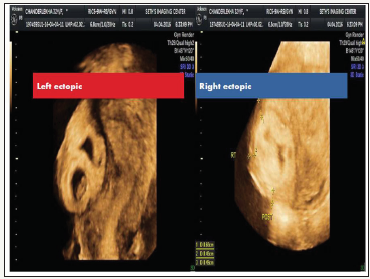

figure 1:Image of transvaginal ultrasound showing ectopic mass in isthmic region on left site and on right side ectopic mass at angle of uterus.

We hereby report a case of triplet live ectopic pregnancy of 6 weeks 5 days gestational age with beta human chorionic gonadotropin (βhCG) more than 200000 units (2sacs in right cornual and 1 in left isthmus) following embryo transfer of three blastocysts (Figure 1). This patient had undergone laparoscopic bilateral proximal tubal occlusion 5 years ago for bilateral hydrosalpinx with frozen pelvis. She also had history of 6 failed IVF-ET cycles at different centers for tubal factor infertility before she was referred to us, for management of this ectopic pregnancy.